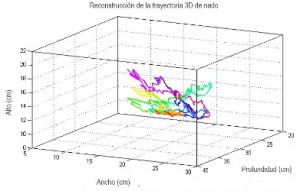

El proyecto de Patricia consistió en la realización de un sistema de video que, según explicó, permite realizar un análisis tridimensional del posicionamiento del pez cebra adulto: “registra cada uno de sus movimientos y es capaz de reconstruir la trayectoria de nado del pez, así como obtener las variables que determinan su conducta. Adicionalmente este sistema es capaz de clasificar automáticamente a los peces tratados con algún fármaco y a aquellos que no lo han recibido”.

Este análisis de los movimientos en modelos animales tiene gran relevancia debido a que revela patrones que pueden llegar a determinar conductas que no son apreciadas a simple vista. En el caso de los peces cebra, la ventaja adicional es que son ideales para pruebas de fármacos, pues la absorción de éstos no es invasiva.

“Esto nos lleva a pensar que la conducta presentada por los peces es debida al efecto del medicamento que se aplica y que no se debe a factores de estrés por manipulación. Aquí radica la importancia de contar con sistemas de análisis de conducta motora diseñados para este modelo animal, pues no solo reduce el tiempo que el experimentador debe dedicar al análisis, sino que además le permite tener mediciones más exactas”, añade Patricia.

Trayectoria de nado del pez cebra

Trayectoria de nado del pez cebra